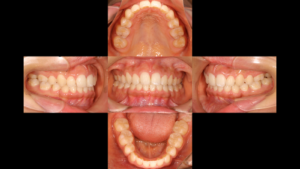

仕上げのガミースマイル改善(レングス)

歯並びが整うだけでは、本当の「美しさ」は完成しません。 今回は同時に**クラウンレングスニング(歯冠長延長術)**を行い、歯の形と歯茎のラインを整えました。出っ歯が治り、さらに歯茎の露出が抑えられたことで、笑った時の印象が劇的に変わっています。

まとめ:僕が「歯を選ぶ」理由

「とにかく早く並べばいい」という考え方もありますが、僕は「どの歯を並べるか」が一番重要だと考えています。

状態の悪い歯を抱えたまま矯正を終えるのではなく、一生モノの健康な歯(親知らず)を主役に据える。前回の症例と同様、今回の治療も「患者さんの10年、20年後の噛み合わせを守る」ための、僕なりの回答です。

治療期間:1年10ヶ月

費用:88万円(税込)